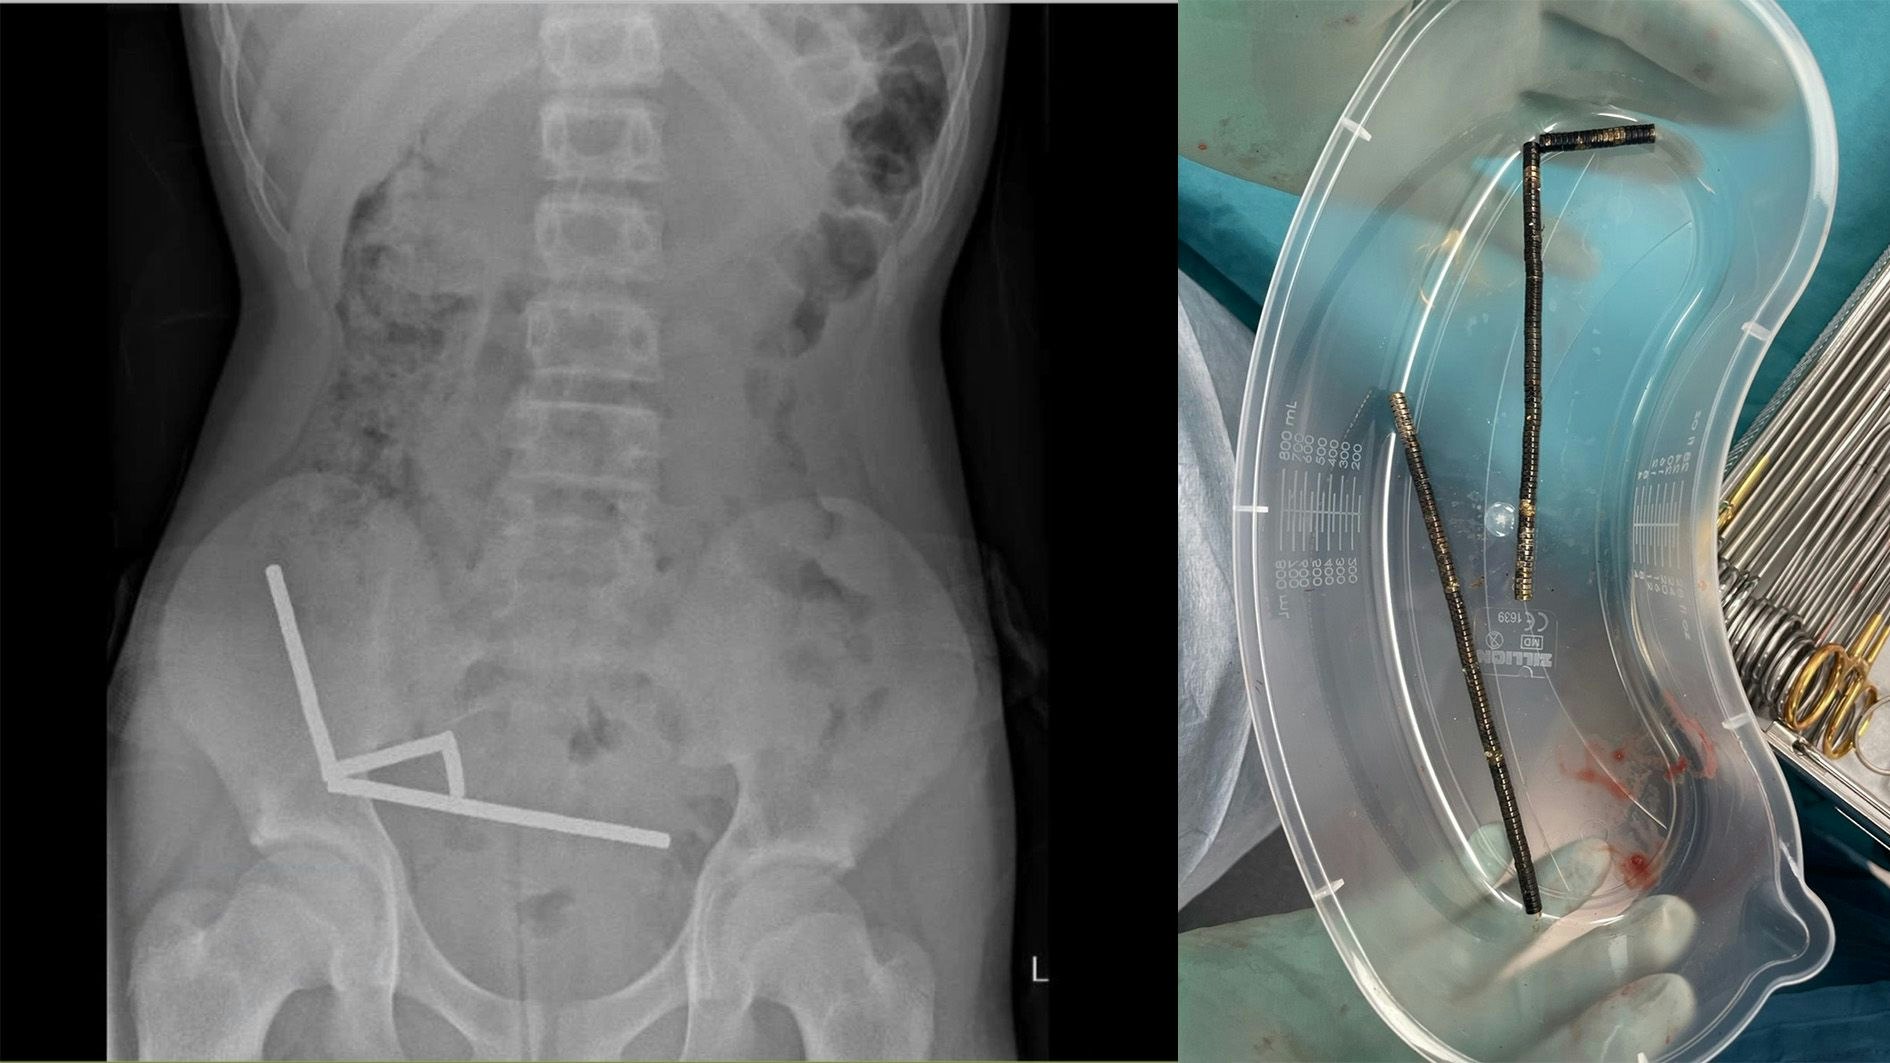

100 Magnete geschluckt: 13-Jähriger in Not-OP gerettet

Bub verschluckt verbotene Magneten – Durch OP gerettet